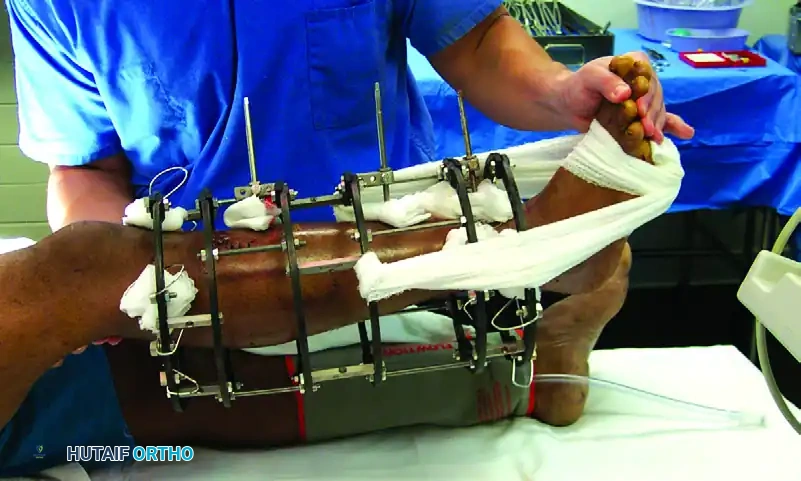

3. Frame Assembly and Reduction

- Apply the pin-to-bar clamps to the pins.

- Attach the longitudinal carbon fiber or titanium rods.

- Perform the fracture reduction under fluoroscopic guidance using manual traction.

- Once length, alignment, and rotation are restored, sequentially tighten all clamps.

- Verify the final reduction and ensure the frame is 2-3 cm away from the skin to accommodate swelling.

* Immediate Post-op: Apply sterile, compressive dressings around the pin sites to prevent hematoma formation and limit skin motion.

* Showering: Patients are generally allowed to shower with the frame after the incisions have sealed (typically 7-10 days), provided they dry the frame thoroughly afterward.